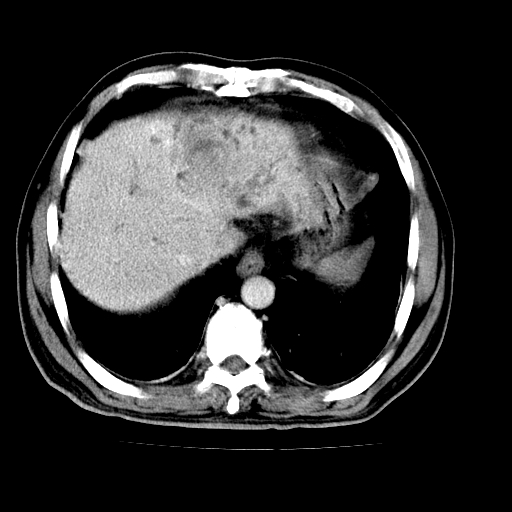

男,66岁,上腹部不适、黄染一周。彩超示:肝左叶占位,肝内胆管扩张,胆总管扩张,胆总管占位?

肝左叶不规则软组织肿块影,边缘不规整邻近肝实质受累分界不清;肝内胆管(左叶)明显扩张成“软藤状”,诊断:肝左叶胆管细胞癌。

肝左叶占位性病变,并胆管扩张,符合胆管细胞癌ct表现,门脉左支受累,左肾囊肿。窗宽太窄了,其他的看不清

左叶胆管细胞癌累及胆总管,门脉左支受侵,慢性胆囊炎胆结石,左肾小囊肿

肝左叶不规则软组织肿块影,边缘不规整邻近肝实质受累分界不清;肝内胆管(左叶)明显扩张成“软藤状”,诊断:肝左叶胆管细胞癌。胆囊钙乳症。

胆囊缩小,其内胆汁浓缩,也提示梗阻部位应该位于胆囊管起始部以上或是胆囊管受累及,支持肝外胆管癌。